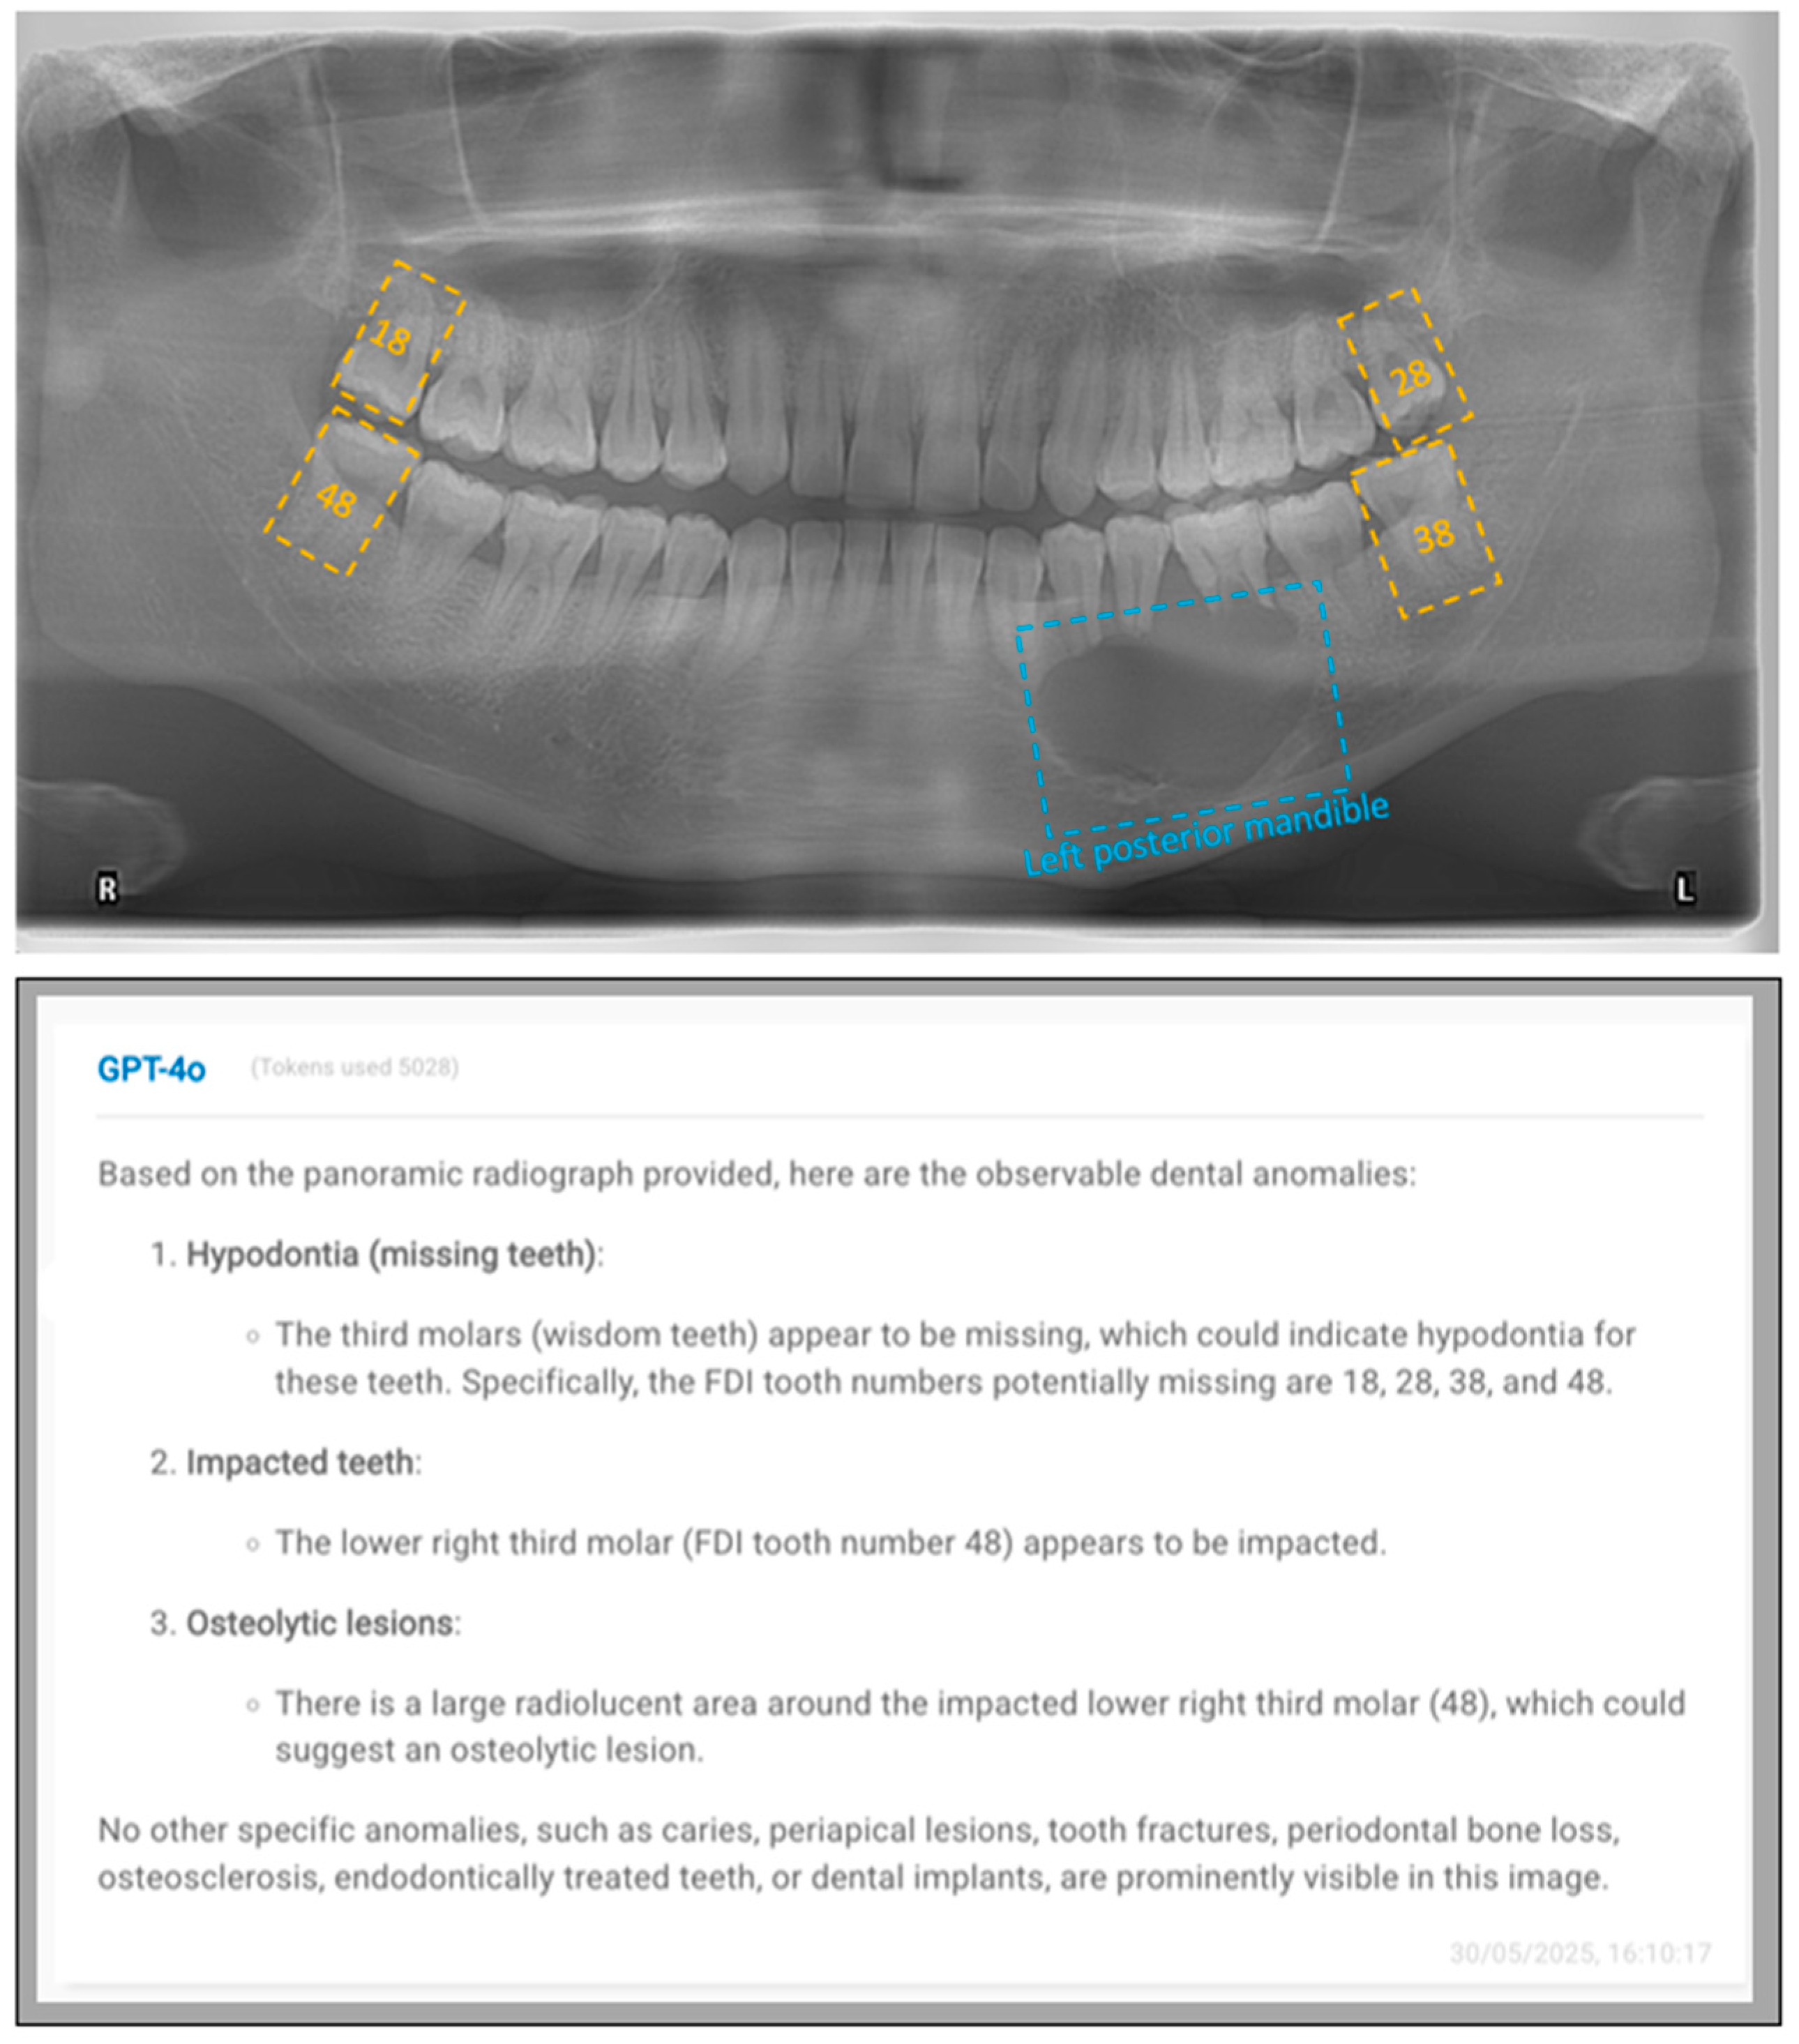

- “This is an anonymized dental panoramic radiograph from a research study. You are assisting in identifying observable dental anomalies as listed below, and specify the FDI tooth number of identified items. Focus only on visual patterns, not diagnoses.

- Developmental anomalies:

- Hypodontia (missing teeth) or anodontia.

- Dental anomalies:

- Caries (radiolucent lesions in enamel/dentin).

- Periapical lesions (e.g., radiolucency at root apex indicating infection or granuloma).

- Tooth fractures, cracks, or retained roots.

- Impacted teeth (e.g., third molars, canines).

- Bony anomalies:

- Periodontal bone loss (horizontal/vertical reduction in alveolar bone height).

- Osteolytic lesions (e.g., cysts, tumors like ameloblastoma or odontogenic keratocyst).

- Osteosclerosis (abnormal bone density, e.g., condensing osteitis).

- Iatrogenic/treatment-related findings:

- Endodontically treated teeth or teeth with restorations (Fillings, Crowns or bridges).

- Dental implants (screw-shaped radiopaque structures).”